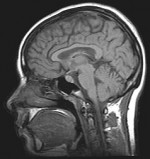

Medical researchers were able to disrupt the moral judgments of test subjects by subjecting the part of the brain responsible for such decisions to magnetic forces:

While the subjects read the story, the scientists applied a magnetic field using a method known as transcranial magnetic stimulation. The magnetic fields created confusion in the neurons that make up the RTPJ, said Young, causing them to fire off electrical pulses chaotically.